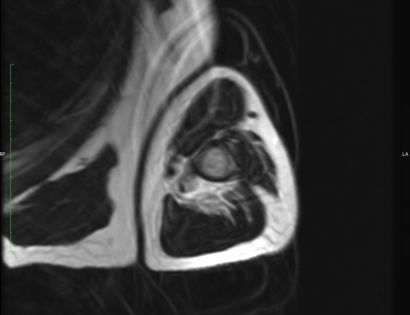

19D) Myeloma SAG T2 FATSAT

Radiographic imaging is used to help form a diagnosis of Myeloma. These include X-Ray, MRI, CT and Bone Scans